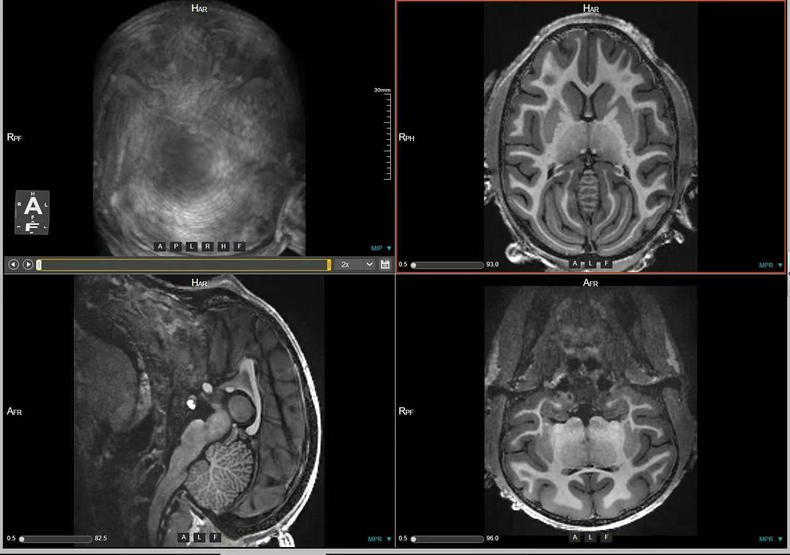

- 关键词:2023-2025年,猕猴,脑部磁共振,3D影像,T1w序列,T2w序列

预定本数据集为2023-2025年对320只4-12岁青年健康雌性猕猴的脑部磁共振扫描收集的数据,主要包括T1w序列和T2w序列影像(3D影像),对于神经学、心理学、行为学等多个相关学科的研究提供丰富的脑数据支撑。

a.物种:猕猴

b.实验动物信息

样本数量:320只

年龄分布:4-12岁

重量分布:3-14kg

性别分布:雌性320只

c.扫描仪规格

扫描仪类型:联影uMRNX 3.0T磁共振扫描仪器

线圈:12通道猕猴专用头线圈

d.扫描程序

动物福利伦理:由中国科学院昆明动物研究所实验动物福利伦理委员会批准。

动物护理和饲养:中国科学院昆明动物研究所实验动物中心

麻醉程序:阿托品(0.5mg/ml)-氯胺酮(0.05mg/ml)-丙泊酚(2mg/ml),阿托品和氯胺酮之间间5-10分钟,氯胺酮和丙泊酚之间间隔5-10分钟。

麻醉和扫描间隔时间:从阿托品算起,大约25分钟,从氯胺酮算起大约15分钟。

扫描体位:仰卧头先进

原始数据,未经加工处理。

数据采集使用联影uMRNX 3.0T磁共振成像仪器,该设备质量符合国家相关标准,所有设备操作者均接受上岗培训,以确保获得合格的高清晰度图像。